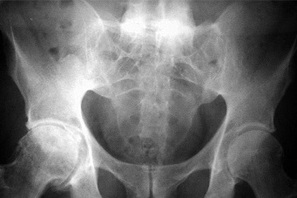

Smerterne i ryggen kan være udtryk for andre tilstande i ryggen, og derfor benytter lægen hyppigt billedundersøgelser i udredningen. En særlig MR-skanning af bækkenled og hele rygsøjlen vil kunne vise gigtforandringer tidligt i forløbet. Almindelige røntgenbilleder af bækkenled og rygsøjle viser ofte først forandringerne efter mange års sygdom.

Normal røntgen af bækkenled

Sammenvoksede bækkenled efter mange års sygdom